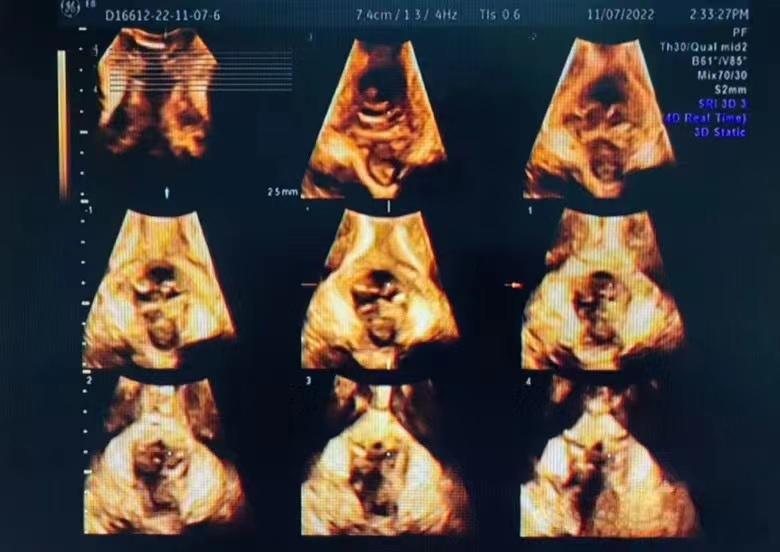

盆底超声检查可以清晰观察到盆底的解剖结构及动态变化,应用二维超声探头在会阴部观察患者盆腔前、中、后三个腔室,来了解盆底组织、器官的结构和功能,同时可以进行四维容积成像,可获得肛提肌裂孔面积,可以进行层厚约2.5mm断层成像,如同CT图像一样,一层一层扫描,从而准确判断肛提肌及肛门内外括约肌的损伤部位及程度。